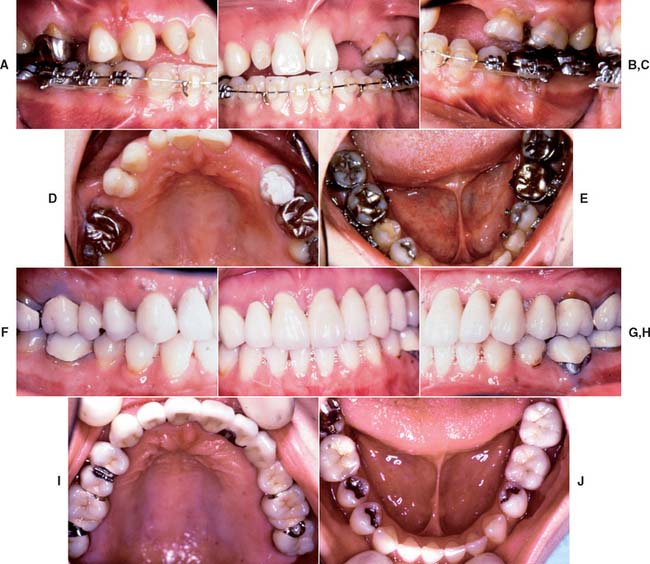

After placement and cementation of a fixed dental prosthesis (FDP), patient treatment continues with a carefully structured sequence of postoperative appointments designed to monitor the patient’s dental health (Fig. 32-1), stimulate meticulous plaque control habits, identify any incipient disease, and introduce whatever corrective treatment may be needed before irreversible damage occurs.

Fig. 32-1 Treatment after placement of multiple restorations. To ensure tissue health and long-term success, proper oral hygiene is mandatory.

Patients with cast restorations should attend recall visits at least every 6 months. Less frequent recall may lead to oversight of recurrent caries or the development of periodontal disease. Patients who have been provided with extensive fixed prostheses (Fig. 32-6) need more frequent recall appointments, particularly when advanced periodontal disease was present. The appointments can be coordinated by the restorative dentist or the periodontist. To ensure treatment continuity, it is imperative to establish in advance who will assume primary responsibility for coordinating recall appointments.

Fig. 32-6 Patients who have received extensive treatment of this nature require more frequent follow-up care.